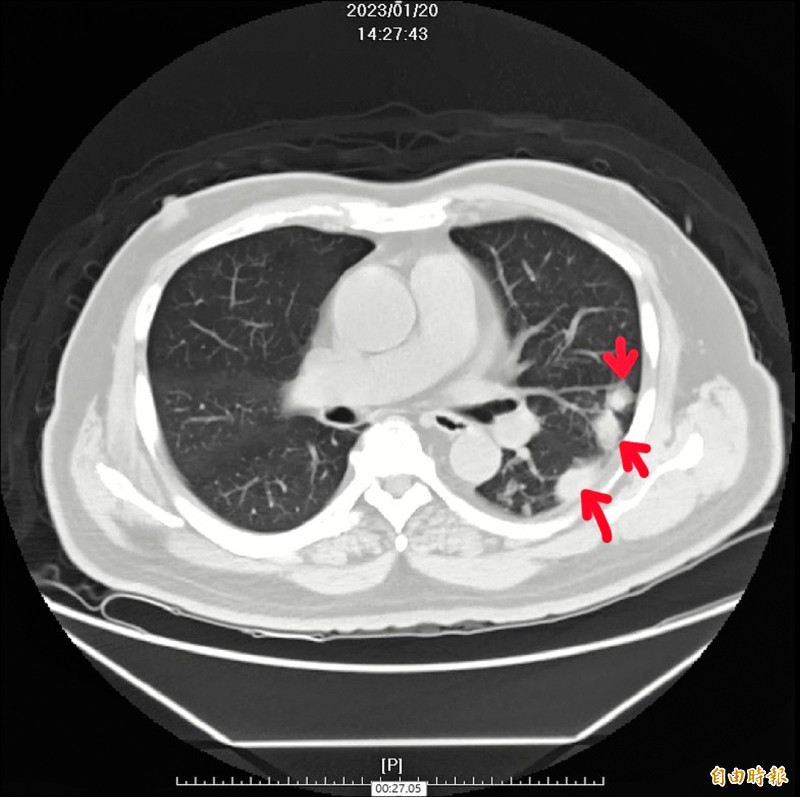

68歲蔡先生3年前檢查發現肺部有多個結節,先後被診斷罹患肺癌及肺結核,用藥治療後,病灶皆未改善,再到台中榮總檢查,經手術切片及細菌培養,確診是感染屬於黴菌之一的「肺部隱球菌」,造成肺結節,經對症下藥,接受6個月抗真菌藥物治療後,終於康復。

蔡先生肺結節一開始被認為肺癌,接受化療及細胞治療,療程結束後肺結節未減少,再到另一家醫院檢查,則認為是肺結核,服用抗結核藥物治療,由於用藥出現噁心等副作用,後來到中榮進一步就醫。

歐偉凡評估蔡先生不咳、不喘,症狀表現並不典型,手術切除病灶取得組織檢體,檢驗確認為肺部隱球菌感染,經抗真菌藥物治療後,病灶消失,病情明顯改善。

歐偉凡指出,隱球菌常存於土壤或鳥類糞便中,在免疫正常者中感染較少見,蔡先生確診是肺部隱球菌感染,可能與他曾從事畜牧業及年紀大有關,透過藥物可完全治癒,但是如果未治療,嚴重可能造成肺炎,甚至可能蔓延到腦炎致死;而之前被誤認為是肺癌,則是為良性腫瘤「類癌」。